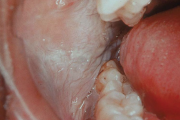

allergia proteesi akrüülvaigust